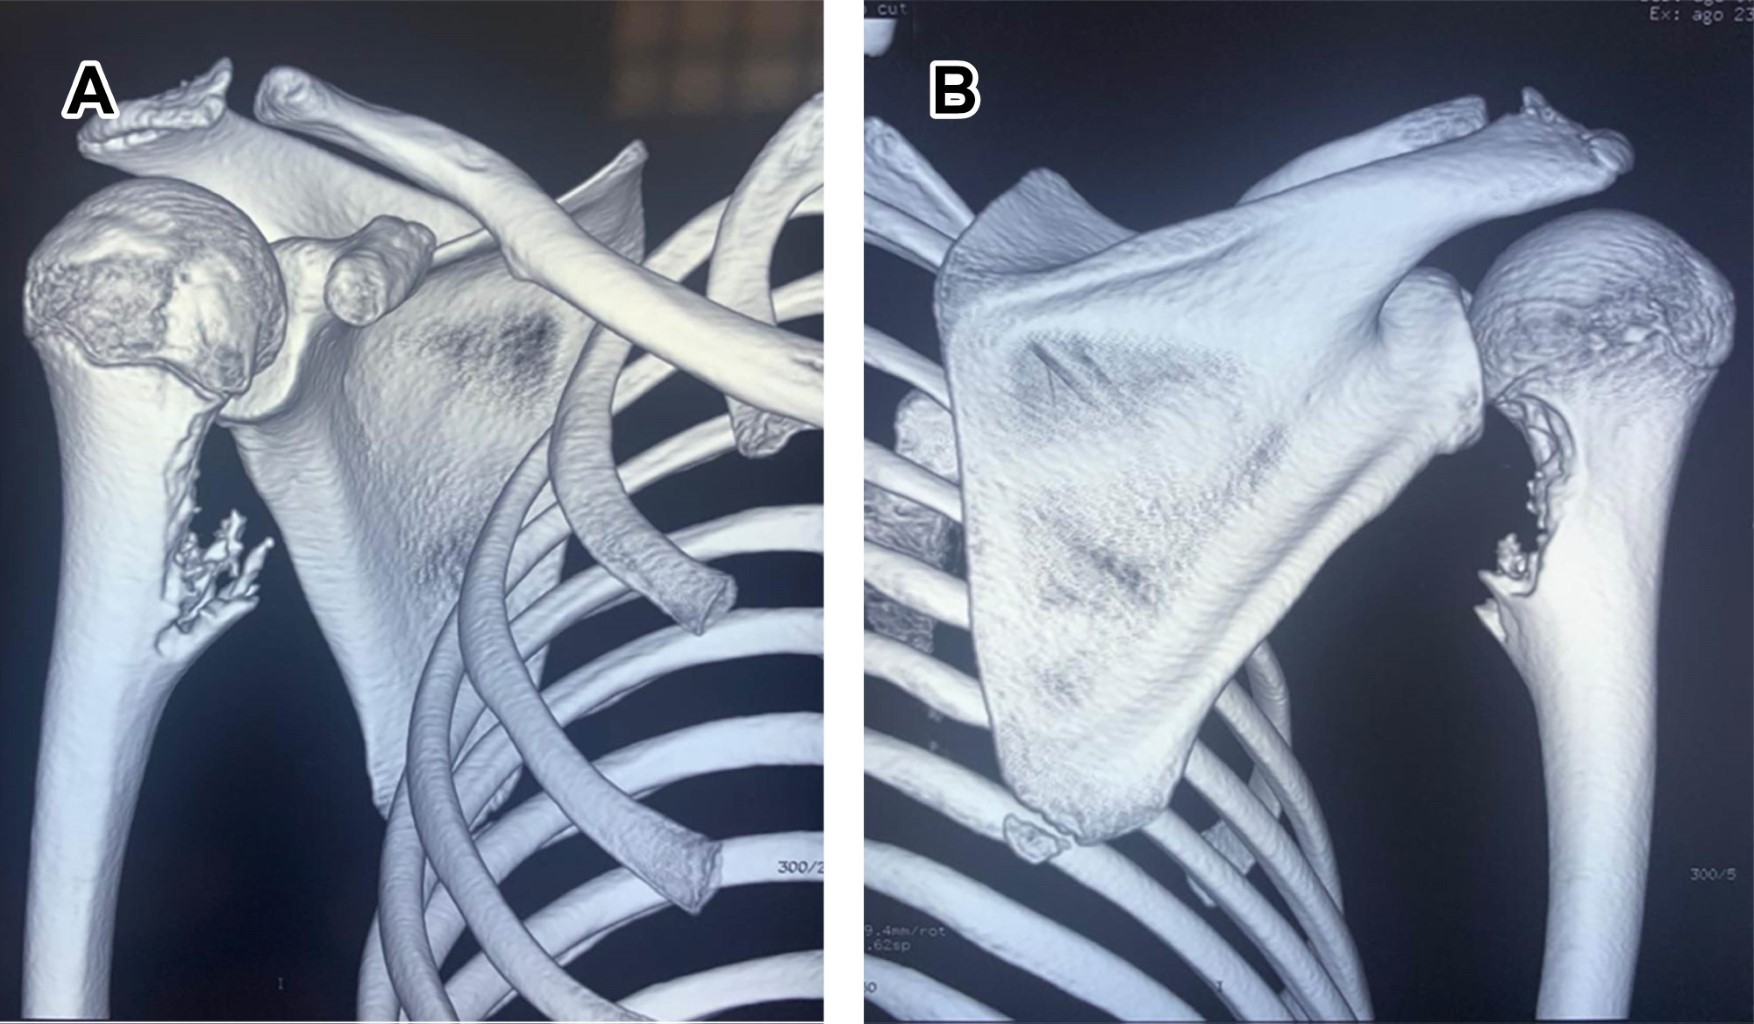

Osteochondroma is a benign tumor, defined as osteocartilaginous exostosis with corticomedullary continuity that reproduces the structure and progression of a physis during growth, considered a developmental disorder rather than a true neoplasia, caused by the separation of a cartilaginous fragment of epiphyseal growth, herniating through the normal bone surrounding the growth plate. It is observed in children and adolescents, without gender difference; most are solitary. The common sites of appearance are the distal end of the femur and the proximal end of the tibia and humerus; it can occur in any bone formed by endochondral ossification.

Figure 3